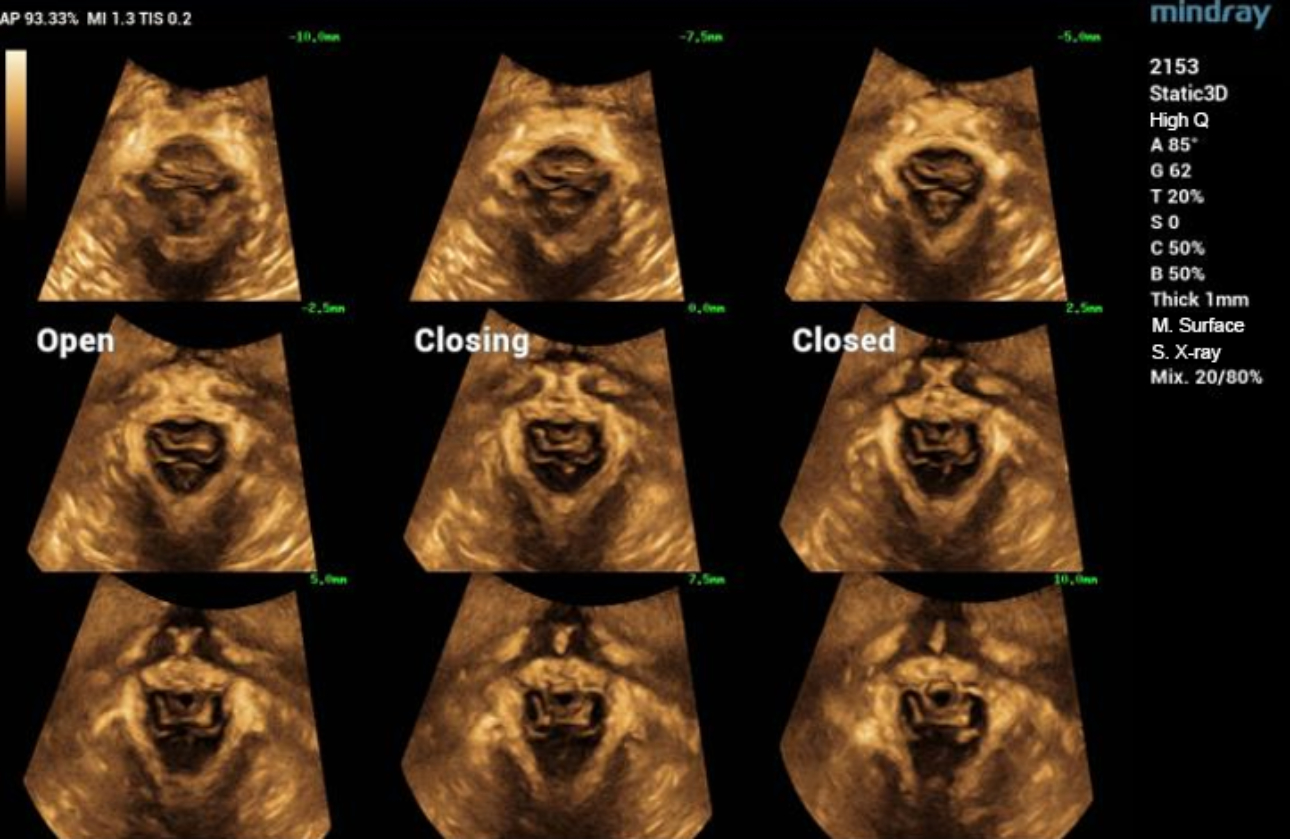

levator-trauma-fig3-pc

형상 1. 항문거근의 골반기저근 초음파 볼륨 영상

형상 2. 정상 levator ani 근육의 Ipage+영상은 3x3모드를 채택하고, 양쪽 levator ani 근육의 균일한 반향과 대칭되는 모습을 보여줍니다. 가운데 3개의 이미지들은 각각 2.5mm의 레이어 간격으로 pubic symphysis의 열림과 닫힘, 그리고 닫힌 상태를 보여줍니다.